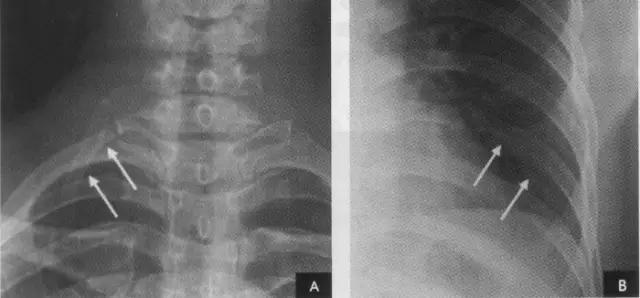

5、左肺下叶左肺下叶相当于右肺下叶所占据的肺野。除上述肺的分叶外,还可有先天变异而出现额外肺叶,称为肺副叶。副叶由肺叶间裂伸入肺叶内所形成。常见有下列4个: (1)奇叶系因奇静脉位置异常所致,发生率约为0.5%。胚胎发育早期,奇静脉跨于右肺尖,在肺曩上发育时,奇静脉应下移至肺尖内侧,最后固定于右侧纵隔内肺根上方。若这种滑移动作受阻,奇静脉即嵌入右肺上叶肺尖部,壁胸膜和脏胸膜也随之陷入,所以奇副裂由四层胸膜所组成,即两壁胸膜和脏胸膜,被奇静脉分隔的右肺上叶内侧部分称为奇叶。后前位胸片上,奇副裂呈细线状影,由右肺尖部向内、下走行至肺门上方,终端呈一倒置的逗点状,是奇静脉断面的垂直投影(如下图):

(2)下副叶(心后叶)系下副裂自膈内侧部向下叶基底部伸入,把内侧基底段分隔成为独立的肺叶所致,发生率为6%~10%。两侧均可发生,以右侧多见。后前位胸片上,下副裂呈细线状影由膈面内侧向上、向肺门方向斜行,其长度随副叶伸入的程度而不同,下副裂的内侧部即为下副叶。